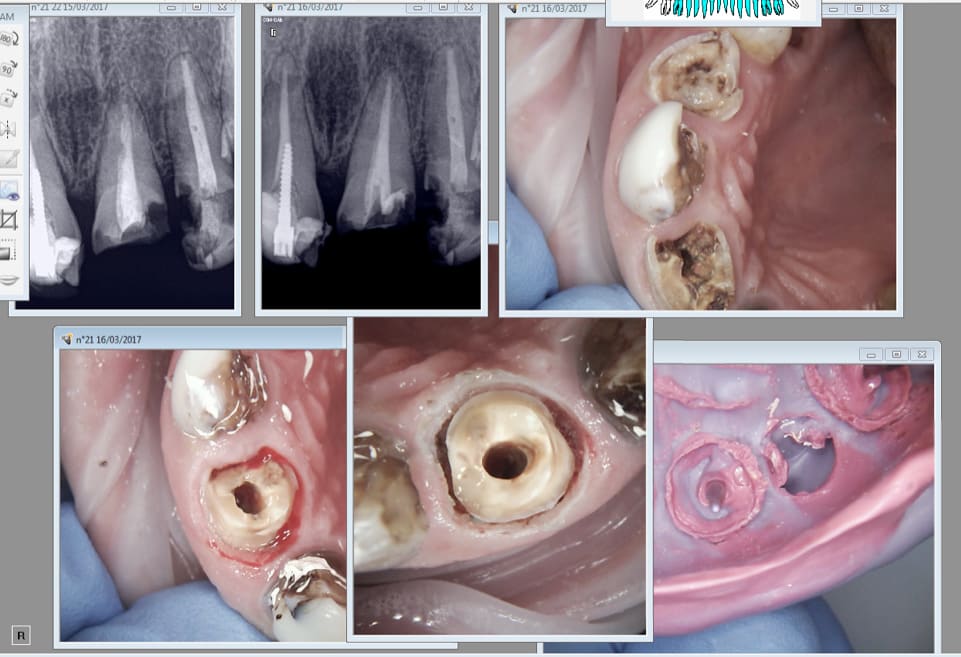

Tu vois casa le laser c'est top. Tu enlèves ce que tu veux ou tu veux. C'est un peu grossier mais avec les loupes ca va s'améliorer. -)

Patiente CMU, je fais plus pour eux que tes socialos de mes couilles. Bâcler le boulot n'est pas dans mon logiciel.

Je ne voudrais pas être cynique chicot mais dans ce cas (la deuxième photo ) c'est le complet assuré dans les 10 ans qui viennent , alors pourquoi ne pas aller direct au but .... Y'a pas de miracle , dent pourries , pas d'hygiène , ni de vie , ni de bouche , ni d'ailleurs .. . même avec une dentisterie 2.0 c'est mort ! Ah mais le complet cmu c'est vraiment pas bien rémunéré ce truc ! une honte .

16/03/2017 à 19h00

Pas sur. De toutes facons ca sera gratuit.

On va passer par les Stellites gratuits avant. Un complet immédiat c'est que des emmerdes. Surtout avec autant de dents à extraire + la plainte pour mutilation volontaire au cul que tu vas te chopper parce que le patient va réellement en chier. . -)